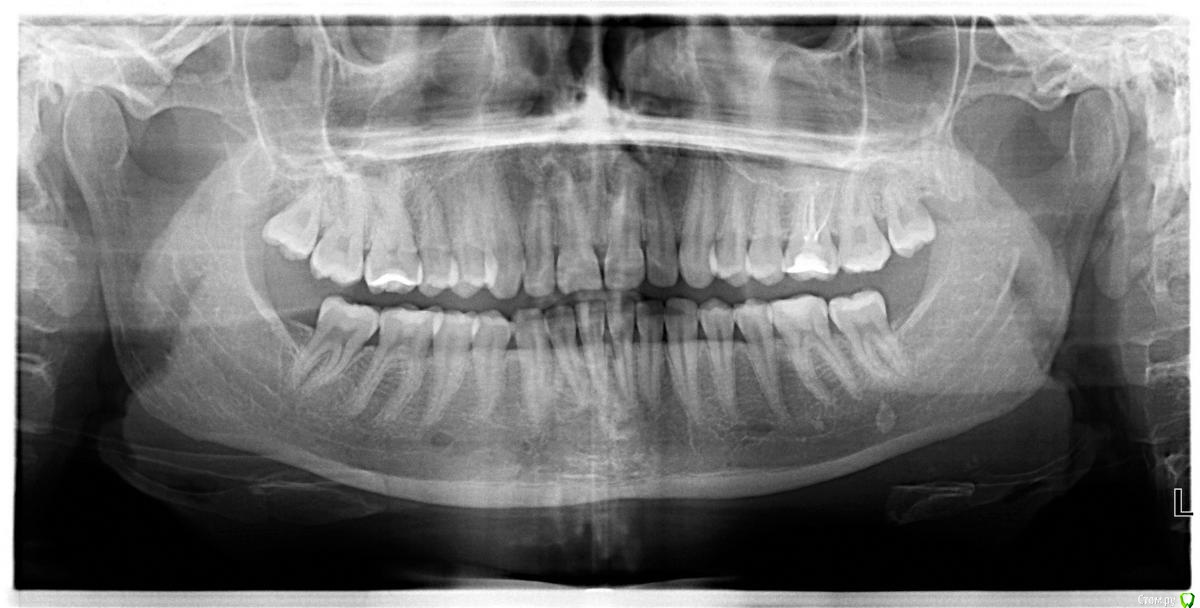

NataliaBer Опубликовано 26 мая, 2016 Поделиться Опубликовано 26 мая, 2016 (изменено) Здравствуйте! Полтора года назад лечила периодонтит в 6 сверху справа, сейчас болит при накусывании и после чистки в этом месте появляется кровь из десны. По снимку стоматолог сказала, что с этим зубом все хорошо, но имеется периодонтит в пятерках, единицах и двойках сверху. Так ли это и стоит ли идти к другому стоматологу? Всем заранее спасибо за ответы Изменено 26 мая, 2016 пользователем NataliaBer Ссылка на комментарий

Гарриевич Опубликовано 26 мая, 2016 Поделиться Опубликовано 26 мая, 2016 Здравствуйте! Полтора года назад лечила периодонтит в 6 сверху справа, сейчас болит при накусывании и после чистки в этом месте появляется кровь из десны. По снимку стоматолог сказала, что с этим зубом все хорошо, но имеется периодонтит в пятерках, единицах и двойках сверху. Так ли это и стоит ли идти к другому стоматологу? Всем заранее спасибо за ответы По этому снимку о периодонтитах говорить сложноДелайте КТ, мы подскажем Ссылка на комментарий